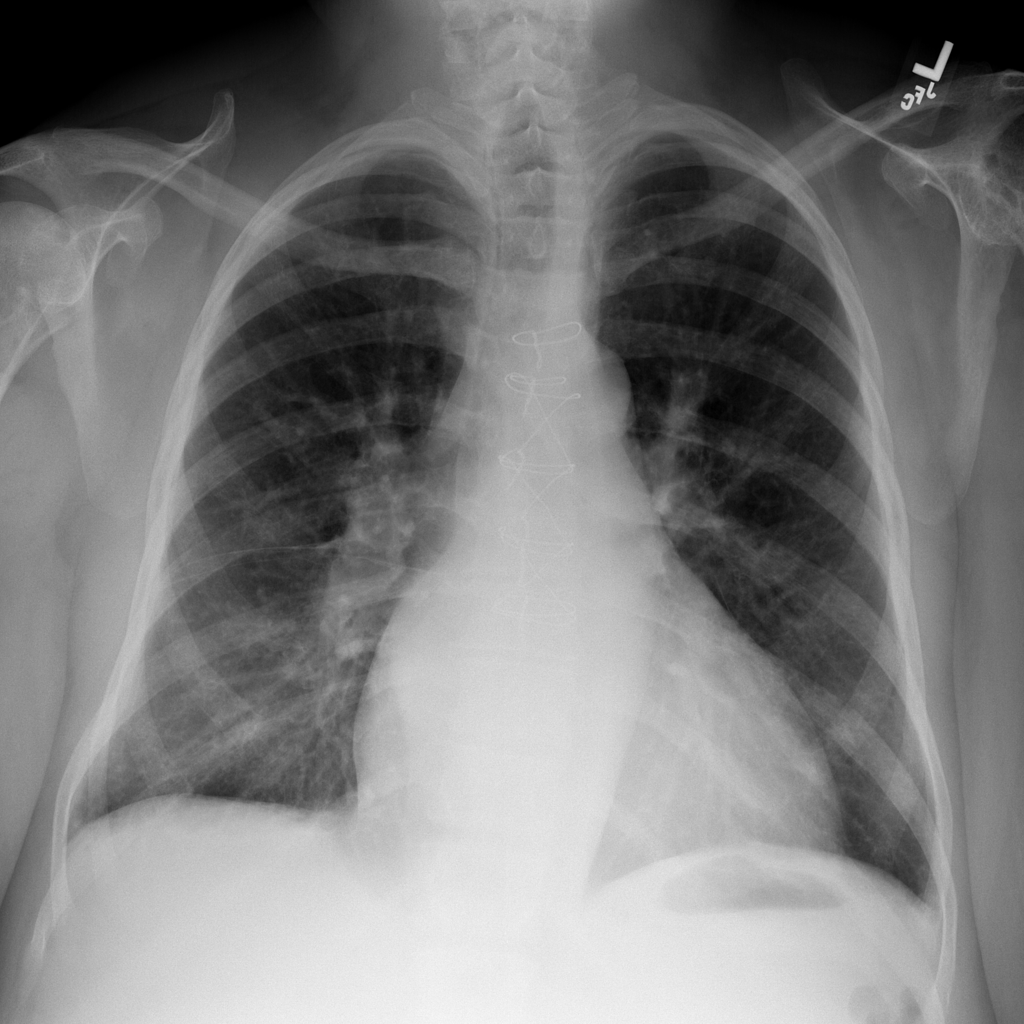

PAT-531A · IMG-006Consolidation

PAT-531A · IMG-006

PA